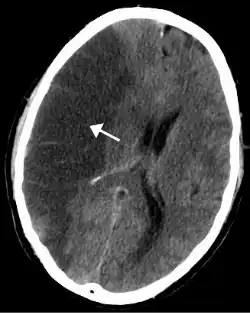

Hersenbloedingen

Hersenbloedingen kennen twee hoofdtypen:[12][13]

- Intracerebrale bloeding, waarbij de bloeding in de hersenen ontstaat, bijvoorbeeld als een ader knapt. Er kan onderscheid gemaakt worden tussen een intraparenchymale bloeding (bloeding in het functionele hersenweefsel) of intraventriculaire bloeding (bloeding in het ventrikelstelsel).

- Subarachnoïdale bloeding, waarbij de bloeding buiten de hersenen, maar wel binnen de schedel ontstaat. Dit vindt plaats tussen het spinnenwebvlies en het zachte hersenvlies. Dit laatste vlies ligt meteen tegen de hersencellen aan en is het zachtste van de drie hersenvliezen.

Deze twee typen hersenbloedingen zijn tevens vormen van intracraniale bloeding. Hierbij vindt de bloeding plaats in het "cranium", het deel van de schedel waar de hersenen in liggen. De andere vormen van intracraniale bloeding, zoals epiduraal hematoom (bloeding tussen de schedel en het harde hersenvlies, het buitenste hersenvlies) en subduraal hematoom (bloeding in de ruimte onder het harde hersenvlies), worden niet ingedeeld onder de hersenbloedingen.[14]

Hersenbloedingen ontstaan als een bloedvat in de hersenen openbarst. Als dit gebeurt krijgen de hersencellen die normaal door dit bloedvat van bloed worden voorzien geen voedingsstoffen en zuurstof meer en sterven af. Het bloed dat uit het bloedvat vloeit duwt het normale hersenweefsel weg. Door de samendrukking van hersenweefsel dat hierdoor kan optreden treedt verdere beschadiging op. Belangrijke oorzaken van hersenbloedingen zijn hoge bloeddruk, afwijkingen van de bloedvaten zoals aneurysmata en AVM's en hersentumoren.